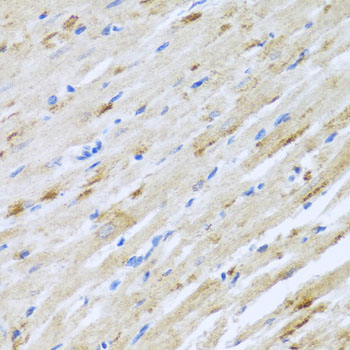

Immunohistochemistry of paraffin-embedded rat heart using STRN antibody.